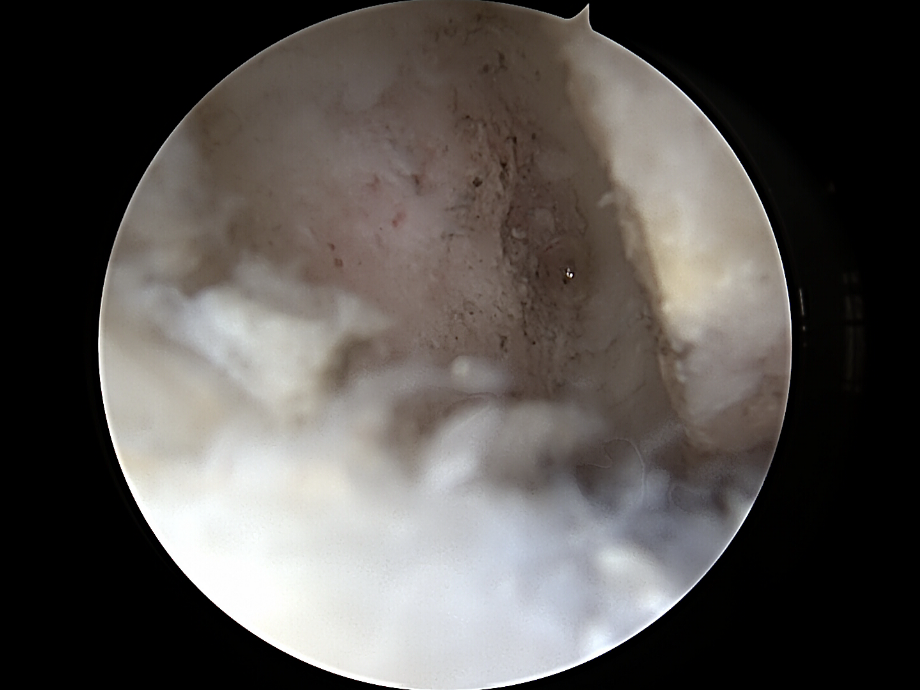

ac gelenkresektion von dr. timmel von ortho-timmel.at

Darstellung des AC- Gelenkes

• Abtragen von Bursa und Weichteilen über dem AC-Gelenk

• Schonung der Kapsel und der coracoclaviculären Bänder (wichtig für Stabilität!)

Abtragen der lateralen Clavikula

• Abtragung von ca. 5-10 mm des lateralen Klavikulaendes

• Instrumente:  motorisierte Shaver

• Kontrolle: ausreichender Spalt ohne Knochenkontakt bei Bewegung